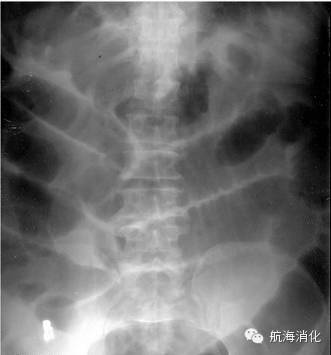

9.为什么要反复拍腹部X光片?

任何不明原因的腹痛,应常规腹部平片检查。腹痛后4-6小时出现气液平和明显肠管积气扩张时,即可诊断肠梗阻,同时,还可区别是小肠梗阻还是大肠梗阻、机械梗阻还是麻痹梗阻,动态观察可反映肠梗阻的病情变化,因此,肠梗阻发生后最好每1-3天拍一张腹部平片,直到气液平和肠积气消失。

麻痹性肠梗阻